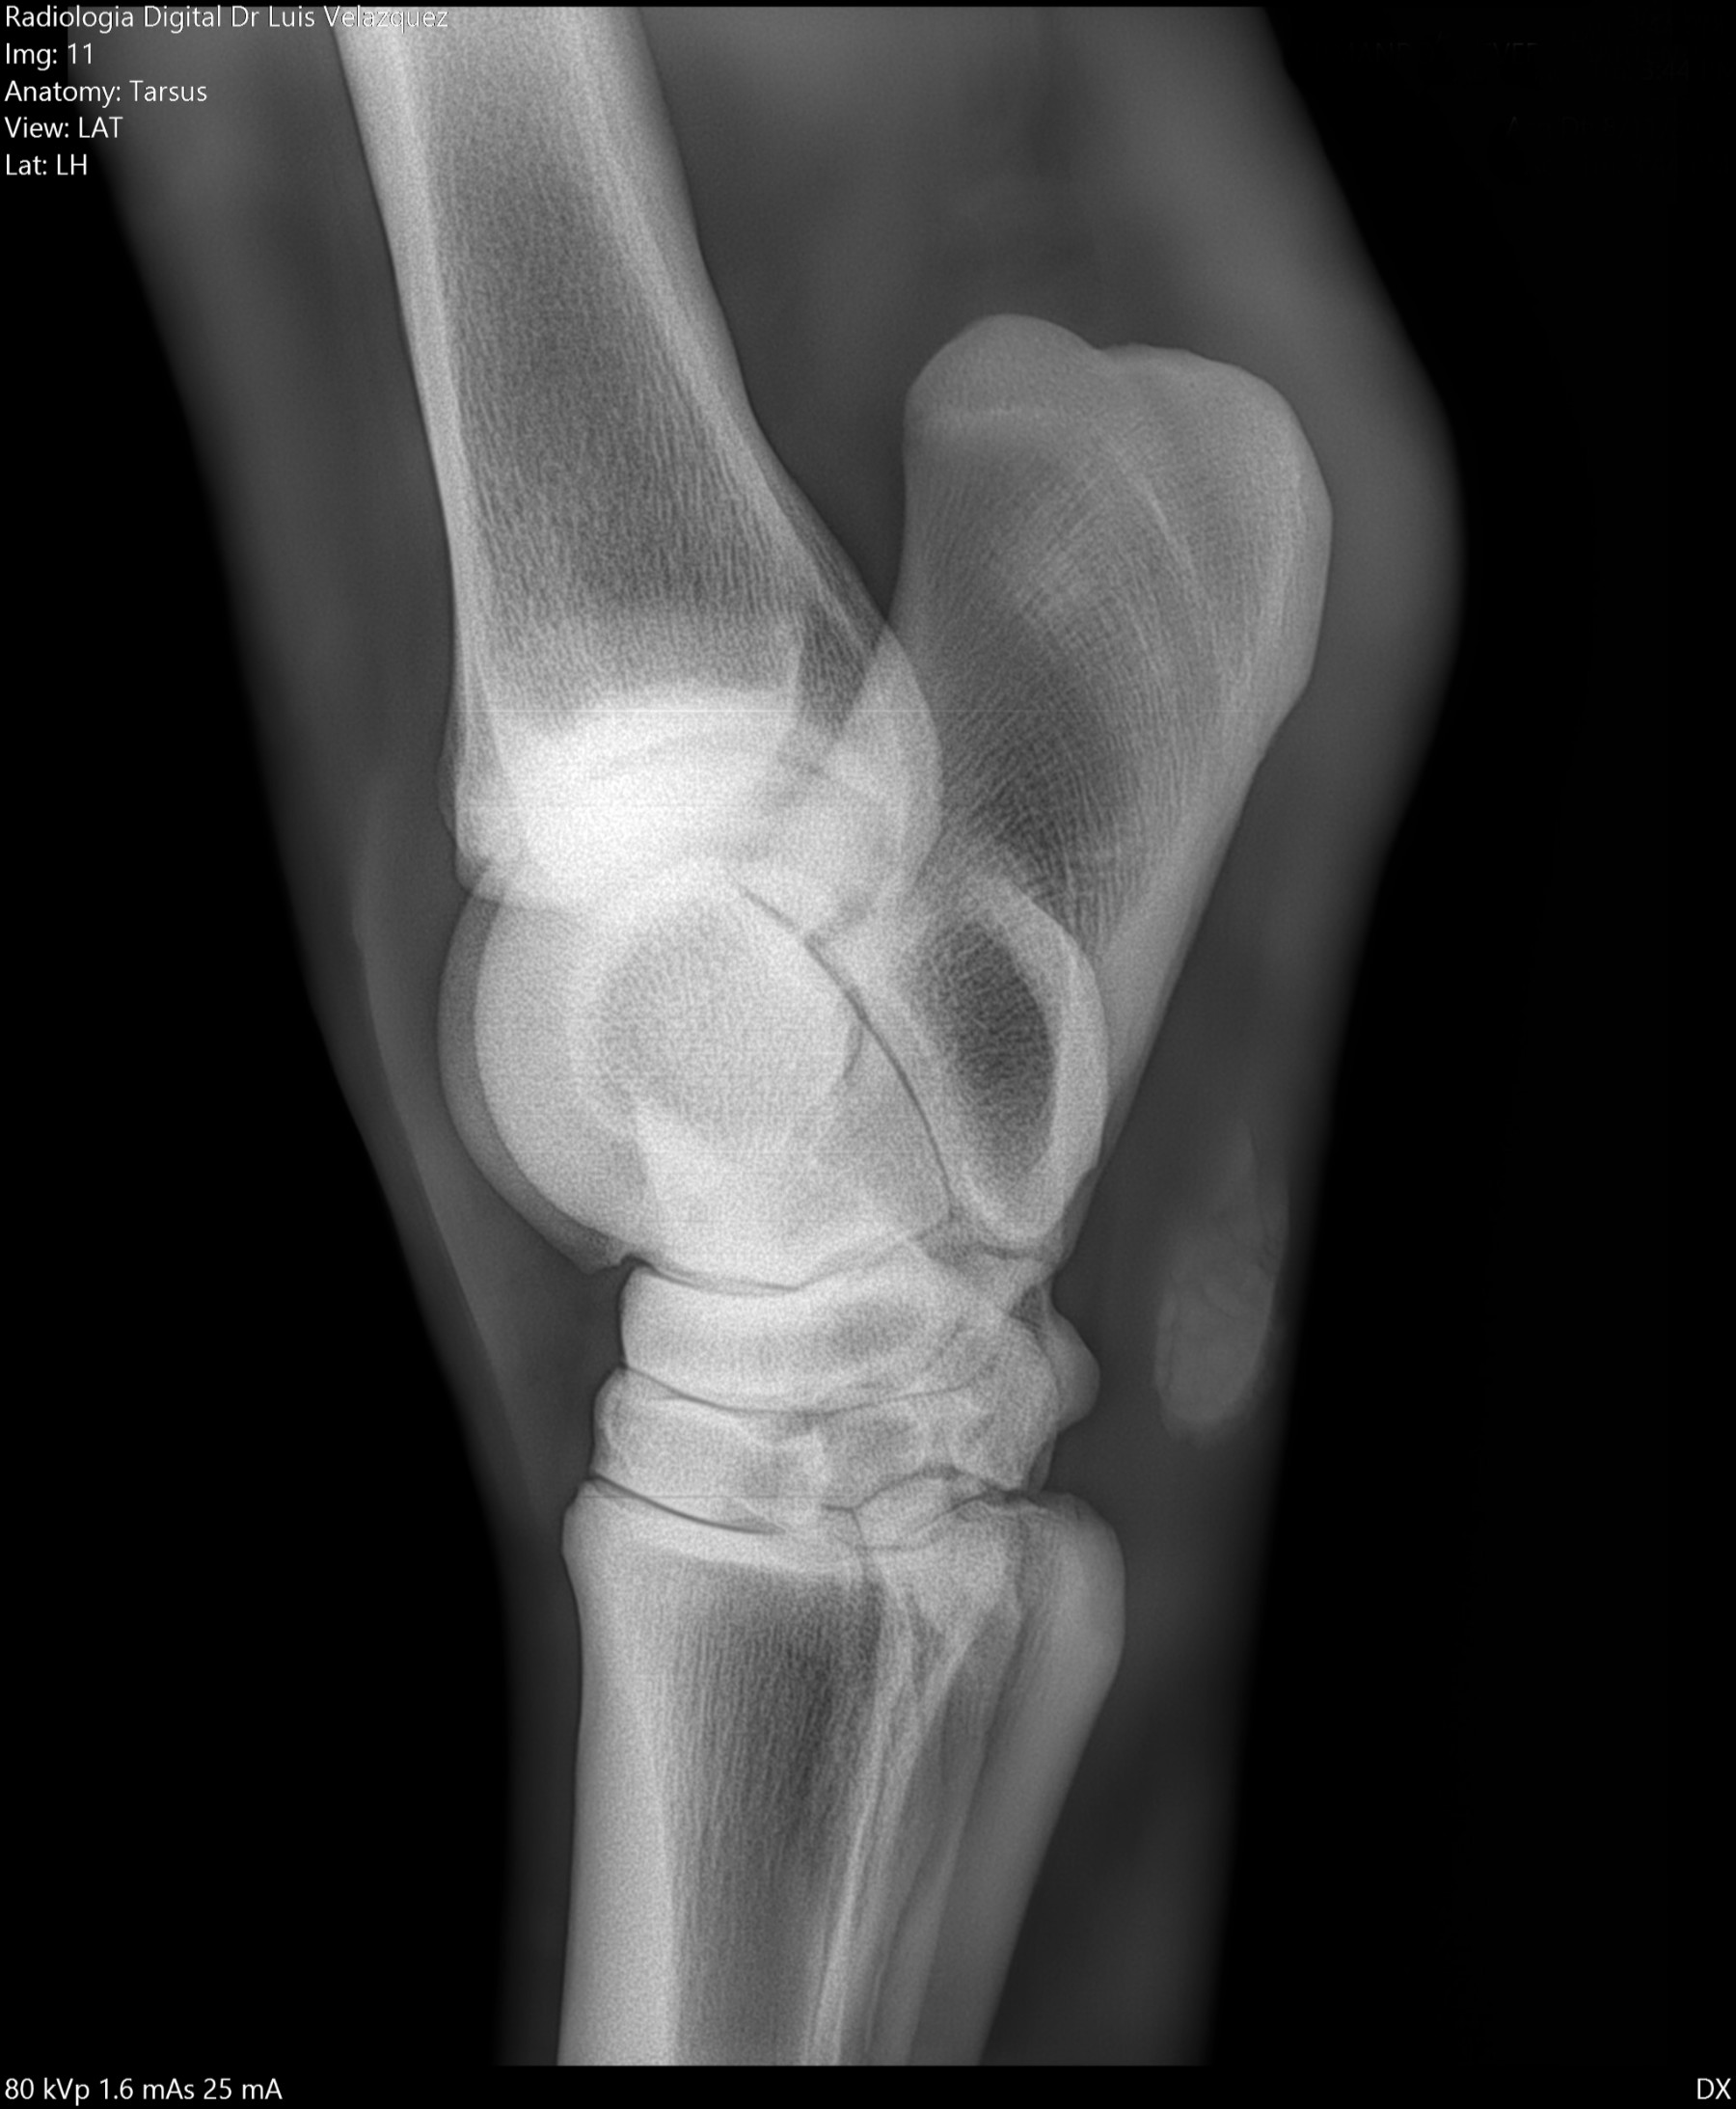

Radiología Digital como Herramienta Complementaria en el Dictamen de Bienes Muebles

Los caballos de salto, en competencia, pueden derribar obstáculos y lastimarse. Si se golpean, no siempre claudican. Considerando al calor como un signo de inflamación, se evaluaron los cambios térmicos de 6 áreas de las extremidades torácicas y pelvianas de 23 caballos de salto en nivel de competencia de 1.05 a 1.60 m de altura, por medio de termografía durante 4 días de competencia (N=2208 áreas).